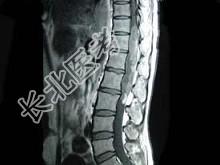

- 单项选择题男,43岁, 背部疼痛,双下肢瘫痪, 查体:下腹部以下深浅感觉障碍, 提睾反射消失,结合图像, 最可能的诊断是 ( )

A、星形细胞瘤

B、脑膜瘤

C、神经鞘膜瘤

D、神经纤维瘤

E、髓内室管膜瘤